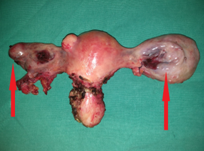

Peritoneal carcinomatosis (gallbladder ca). Ovarian metastases (Courtesy Dr. V. Penopoulos)